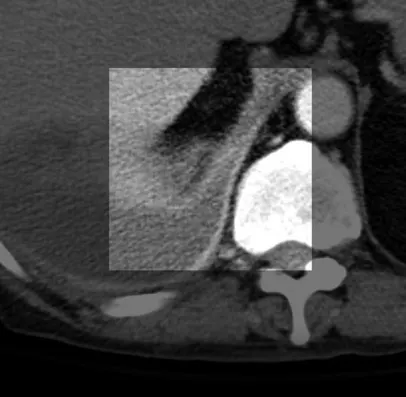

CT 상 Empyema 와 Lung abscess 감별하기

abscess는 갑자기 Bronchovascular 구조물을 interrupt한다.

empyema는 대개 인접한 폐를 변형 시키거나 압박한다

empyema 는 visceral과 parietal pleura를 두껍게 만들면서 서로 분리시킨다

abscess는 두껍고 불규칙한 wall

empyema는 대개 매끈한 walls